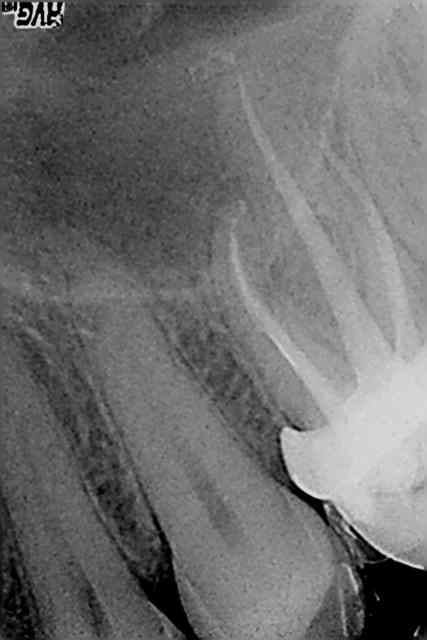

Canal MV au milieu c'est quoi cette connerie?

pas vu, peut etre un bout de thermocompacteur mais il me semble un peu petit sinon superposition des deux canaux? demain je te mats l'autre radio avec une autre incidence je regarderai, mais toute façon pas grave du tout (sauf pour mon instrument)